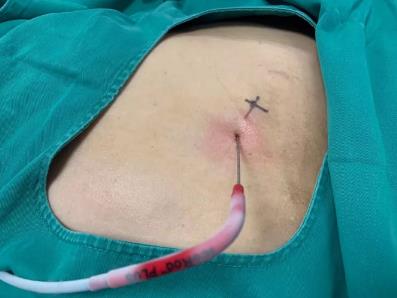

2017年9月29日,从CT影像看到右肾情况更为严重。为减缓肿瘤增长的速度,专家进行商议后,最终决定由牛立志教授主刀为安图叔叔进行了右肾肿瘤冷冻消融术。手术开始后,牛立志教授在CT和超声引导下,同时使用两根冷冻针固定病灶,精准灭活肿瘤;术后很成功无不良反应。术后一周进行第二次双肾肿瘤冷冻消融术。安图叔叔儿子笑道:“当时真的很紧张,医生劝慰我无须担心,都交给他们,我们都很清楚知道父亲的病情,真的很感谢也很庆幸我父亲遇到复大的医护人员,免受开刀之痛。住院期间医护人员很尽心尽力的照顾父亲,手术的成功离不开他们的辛劳付出。”

冷冻治疗手术中